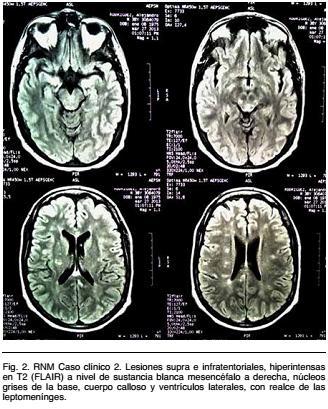

Se realiza RNM encefálica, que evidencia múltiples lesiones supra e infratentoriales, hipo e isointensas en T1 e hiperintensas en T2 (FLAIR). A nivel de la sustancia blanca subcortical, mesencéfalo a derecha, núcleos grises de la base, cuerpo calloso y adyacente a ventrículos laterales, varias se impregnan con contraste y existe realce de las leptomeninges (Figura 2).